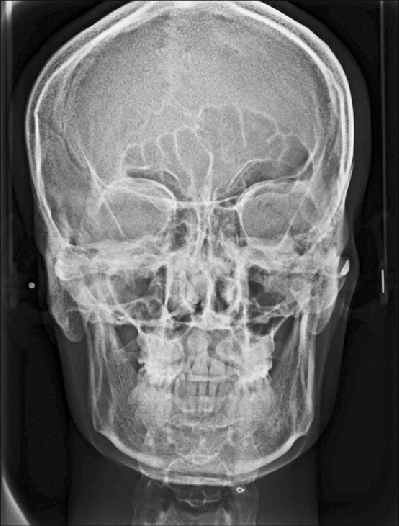

RADIOGRAFÍA DE CALDWELL

(FRONTONASAL)

Esta proyección radiológica específica para la visualización de los senos frontales y etmoidales. Junto con las proyecciones de Waters y lateral de cráneo, forma parte de las radiografías empleadas para el estudio de los senos paranasales. Se pueden observar los senos frontales, celdillas etmoidales, suturas frontomalares, los rebordes supraorbitarios, fosas nasales y orbitas.

Entre sus principales indicaciones se encuentran:

- Evaluación de fracturas y lesiones en la parte posterior de la mandíbula.

- Evaluación de asimetrías mandibulares

- Evaluación de senos maxilares, celdillas etmoidales y seno frontal

Ventajas:

Es útil para observar cara y orbitas y asimetrías mandibulares y posibles desviaciones del tabique nasal.